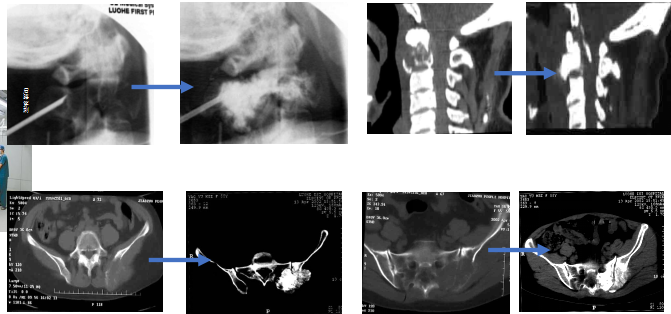

(六)开展网袋技术治疗脊柱转移癌

开展此项新技术,解决了对椎体皮质骨广泛破坏的患者不能行PVP治疗的难题,市内率先开展,截止到2018年底开展手术十余例。

(十)省内首家、国内第四家开展PVP技术

率先将PVP术应用到颈2椎体水平,并陆续开展PKP、经皮网袋骨水泥技术、单侧穿刺弯角注入器双侧注入骨水泥等微创技术。

(十一)可弯曲性骨水泥注入器治疗骨质疏松性椎体骨折技术

球囊多点撑开结合过伸体位治疗椎体骨折技术。

可弯曲性骨水泥注入器治疗骨质疏松性椎体骨折技术,发表在《中华放射学杂志》。

球囊多点撑开结合过伸体位治疗椎体骨折技术,发表在《中国全科医学》。